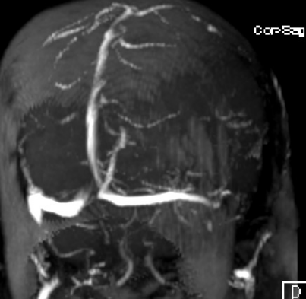

2015-1-30 DSA